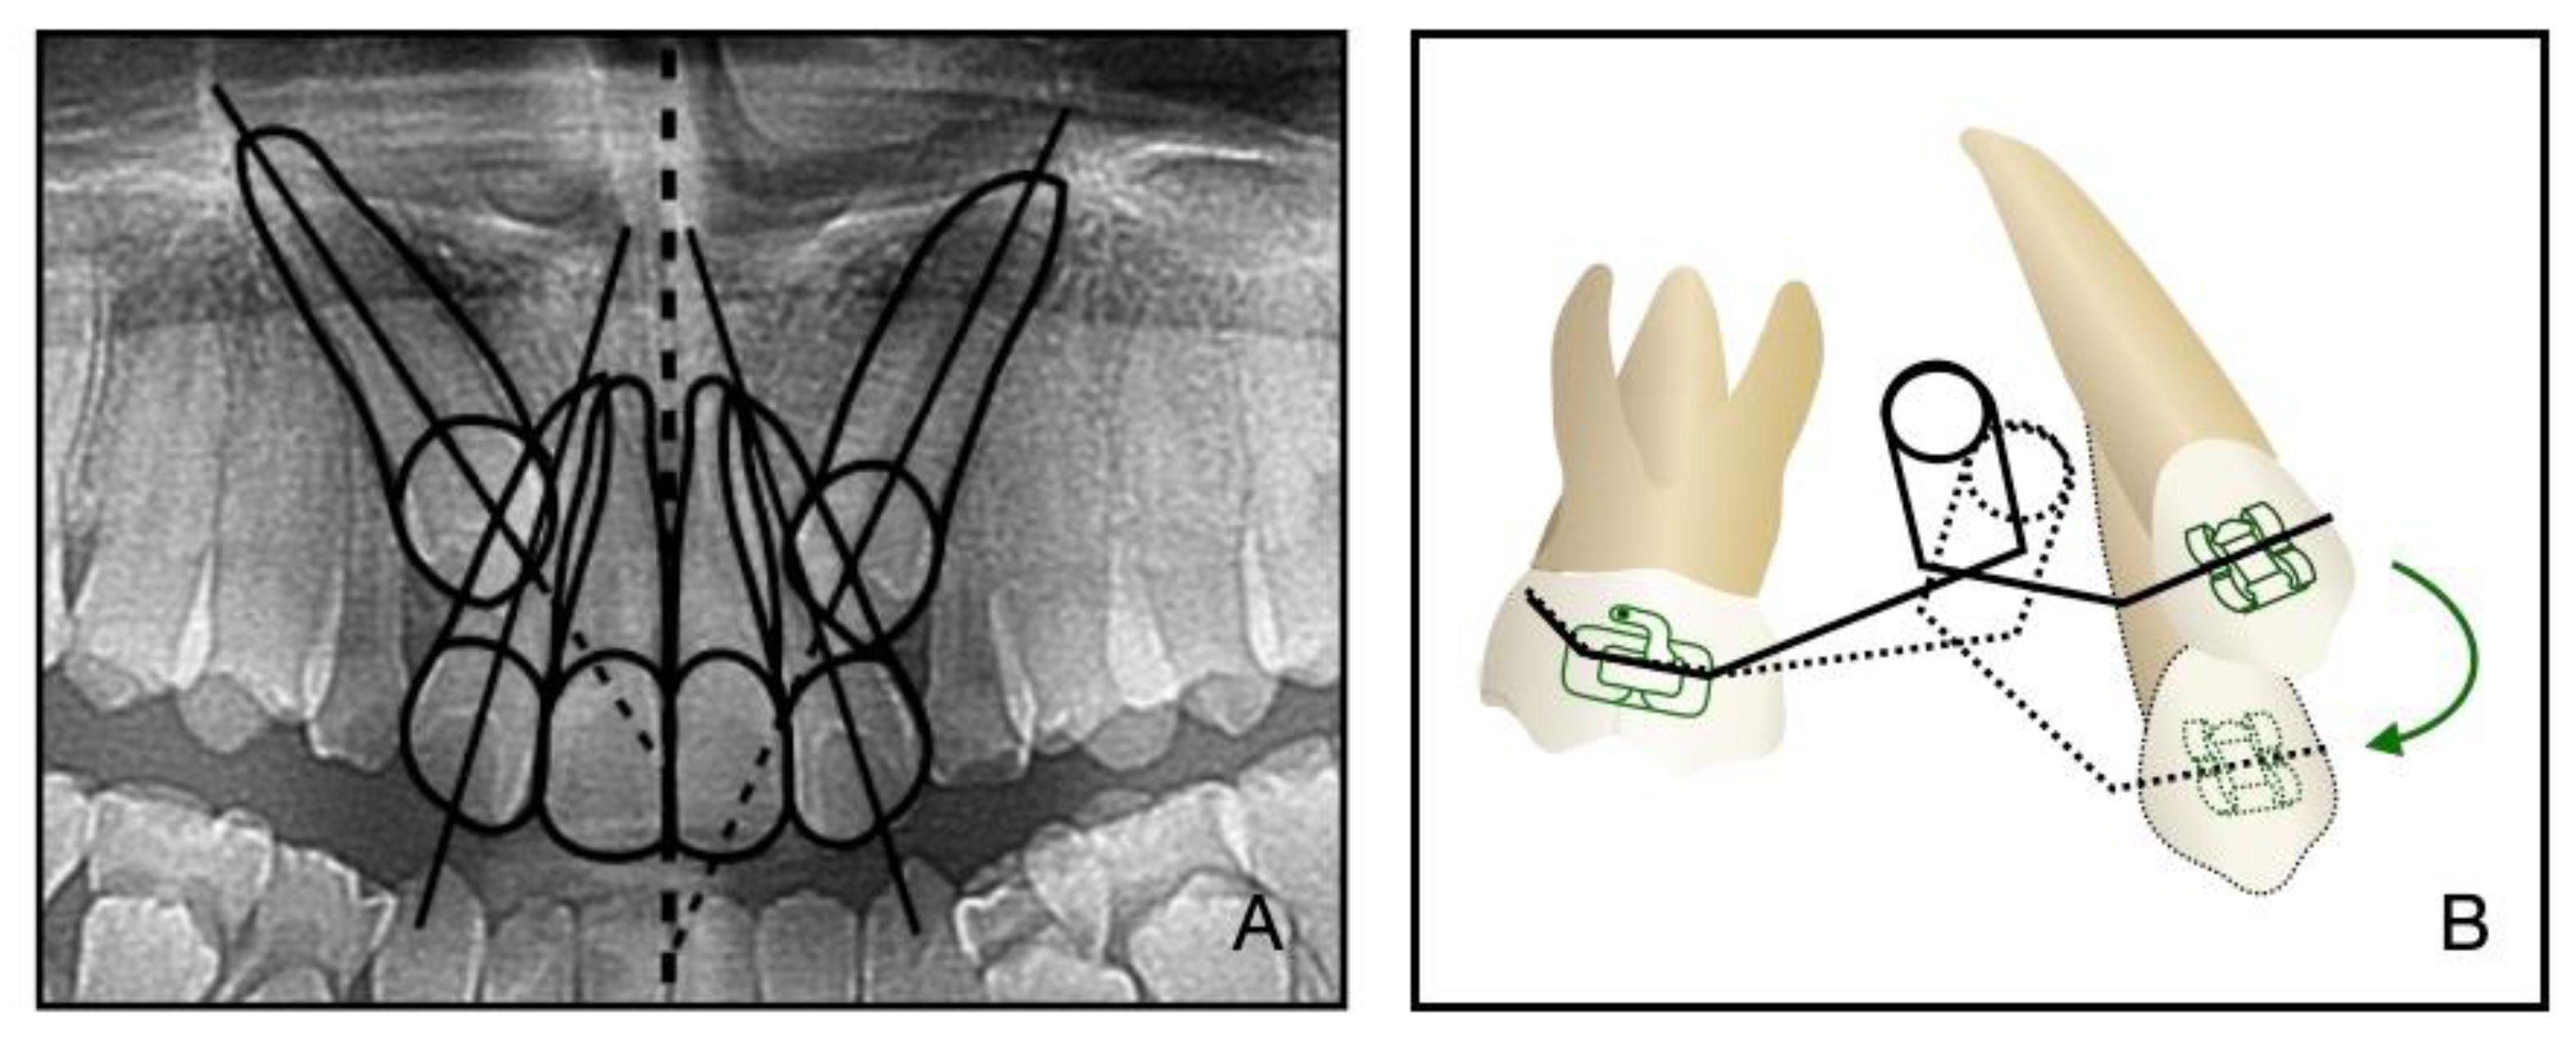

In addition to the maxilla-mandible relationship, the arch and the dentition play an important role in long-term stability. The etiology of the impacted teeth was related to the arch-length deficiency, which occurs in hypo-developed maxilla and may lead to bilateral impacted canines, which happened in this case. A treatment alternative is extraction; however, after extraction, there is a need to figure out an approach to replace the pivotal esthetic and the occlusion function of the missing canines, such as implant-retained crown restoration, conventional bridge, or premolar substitution through orthodontic treatment. The panoramic radiograph showed the canine crown was in the buccal side and distal to the midline of the lateral incisor, which noted a higher rate of successful traction, even up to 91% [3]. However, it takes space to decompensate and tract maxillary anterior teeth, so the extraction project was beneficial to create space [14]. Meanwhile, extraction guided the posterior dental arch to move relatively forward, which was equivalent to increasing the arch of the upper jaw and conducive to the establishment of a normal overjet and overbite of the posterior teeth. All things considered, a removal of the deciduous canines and the first premolars was decided, and then surgical exposure and a segmental arch technique were performed to tract the canines (Figure 12). The pre-surgical planning was mainly to tract the impacted teeth and create enough overjet and overbite for jaw movement, which was established a stable jaw–tooth relationship and improved the profile. The pre-surgical treatment went on for 2 years to achieve the traction of canines and reach the proper timing for the orthognathic surgery, which seemed longer compared to routine cases. Finally, we placed the canines correctly and established an ideal occlusion. Proper overjet and overbite, coordinate width, and close occlusion helped maintain the stable dentition relationship and further ensured the stability of the jaw’s position and soft tissue aesthetic.

Figure 12. (A): The relative position of the canine crown and lateral incisor in a panoramic radiograph. (B): Biomechanism of canine traction through segmental arch. The green arrow illustrates the path of canine movement.